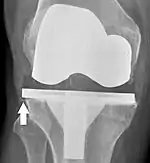

El aflojamiento de la prótesis puede estar indicado en la radiografía por espacios radiotransparentes delgados alrededor del implante, o más obviamente por el desplazamiento del implante.[48]

El reemplazo de rodilla se evalúa de forma rutinaria mediante rayos X, incluidas las siguientes medidas:

CRT: Ángulo cadera-rodilla-tobillo, que idealmente está entre 3° en varum y 3° en valgum desde un ángulo recto.[54]

- CFF: ángulo del componente femoral frontal. Por lo general, se considera óptimo cuando se encuentra entre 2 y 7° en valgo.[55]

- CTF: ángulo del componente tibial frontal, que se considera óptimo cuando se encuentra en ángulo recto. En general, se ha encontrado que una posición en varo de más de 3 ° aumenta la tasa de falla de la prótesis.[55]

- La entalladura femoral anterior (el componente femoral que causa una reducción del grosor del fémur distal en la parte anterior) parece aumentar el riesgo de fracturas cuando excede aproximadamente 3 mm.[56]

- CTL: ángulo del componente tibial lateral (o sagital), que está idealmente posicionado de modo que la tibia esté flexionada de 0 a 7° en comparación con un ángulo recto con la placa tibial.[55]